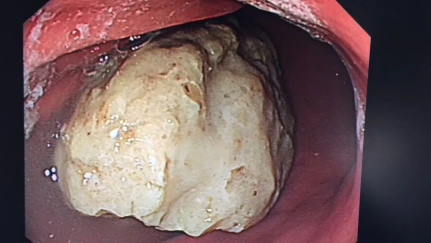

【健康科普】健康提醒!秋冬季,这种水果不能贪多,小心“胃石”找上你(图4)

个人经验是5%碳酸氢钠溶液反复冲洗吸引(泡软)

“石头壳”很硬,用活检钳慢慢夹碎出一条缝隙

目的是内部可以接触到碳酸氢钠溶液,并且,给下一步出场的圈套器留下一个切割位置

【健康科普】健康提醒!秋冬季,这种水果不能贪多,小心“胃石”找上你(图5)

1分2,2分4,4分8,8分16…保证碎块直径小于1cm,这样能保证在下一步碳酸氢钠软化后能顺利地经过肠道排出。